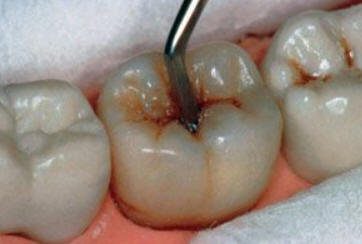

Sólo se lleva a cabo en  cavidades pequeñas ( que involucra solo la dentina ) y en aquéllas que son accesibles para los instrumentos de mano. Con el instrumental de mano se elimina la dentina desorganizada e infectada hasta llegar a la dentina desmineralizada. Ver figura inferior.

Se aísla el campo operatorio con rollos de algodón. Se limpia la cavidad con una torunda de algodón embebida en agua y luego se seca con torunda. Se utiliza la hachuela para ampliar la cavidad de caries, luego se elimina la caries con  cucharitas o excavadores.

Eliminación del tejido cariado en fosa distal